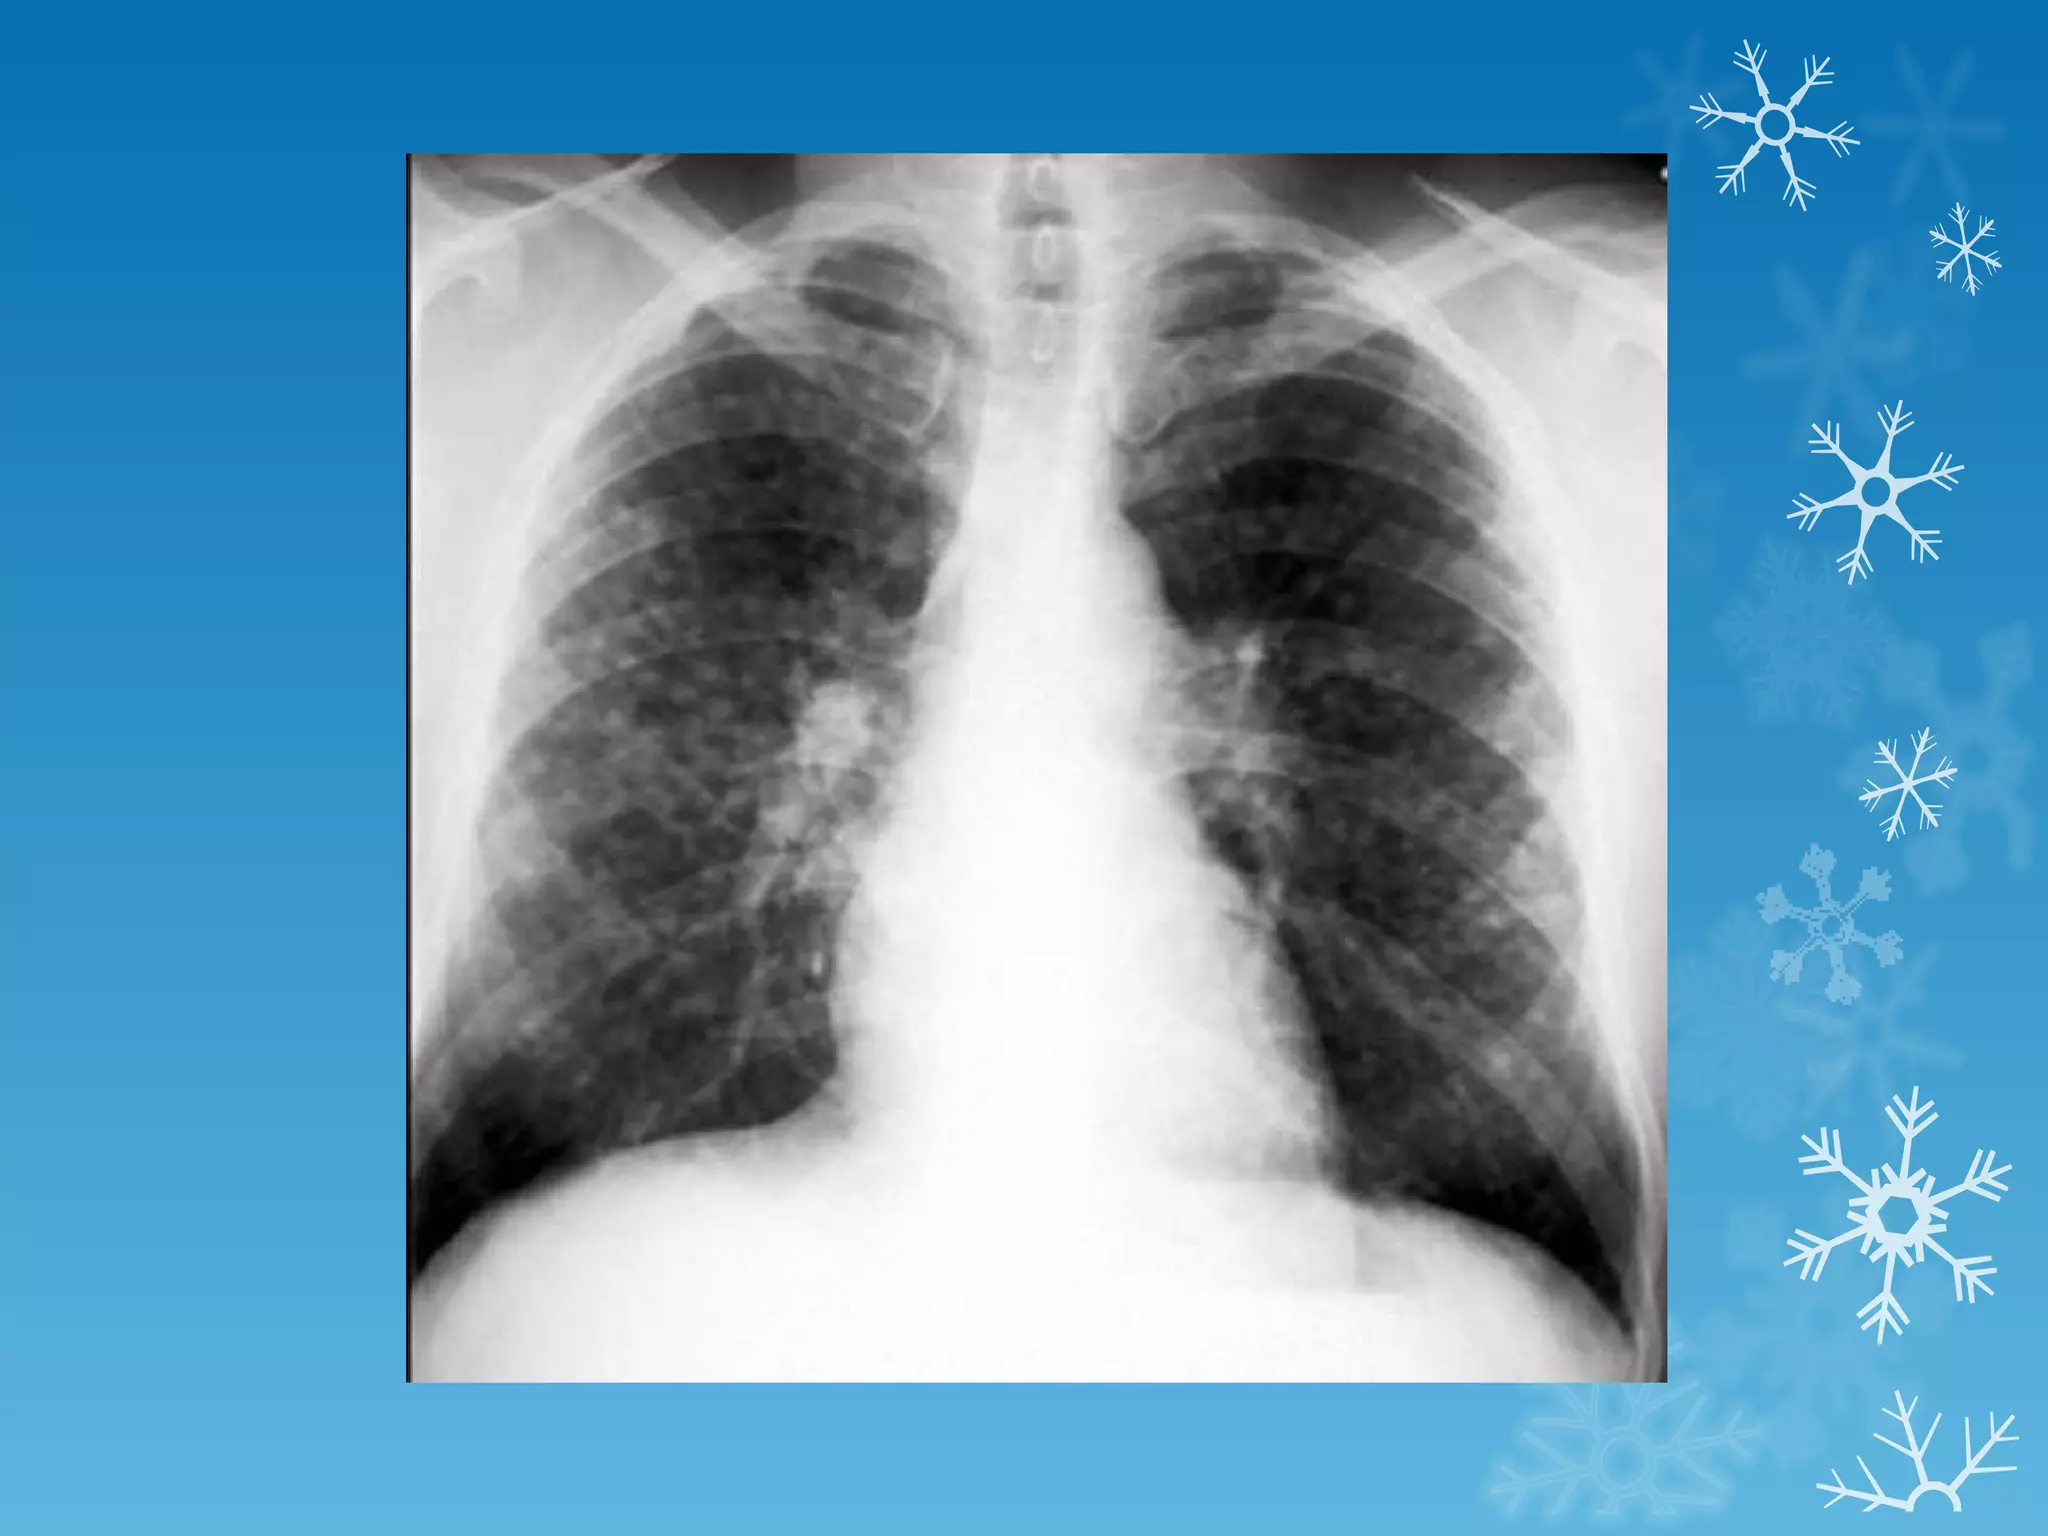

This document discusses chest x-ray interpretation and provides guidance on evaluating x-rays. It explains that tissue density determines how an x-ray beam penetrates, with denser tissues appearing whiter and less dense tissues appearing blacker. It also outlines different chest x-ray views and factors to consider like patient orientation, age, gender, and rotation. Abnormalities are described as appearing too white, too black, too large, or in the wrong place. The document stresses a systematic approach of identifying, localizing, describing lesions, and providing differential diagnoses.